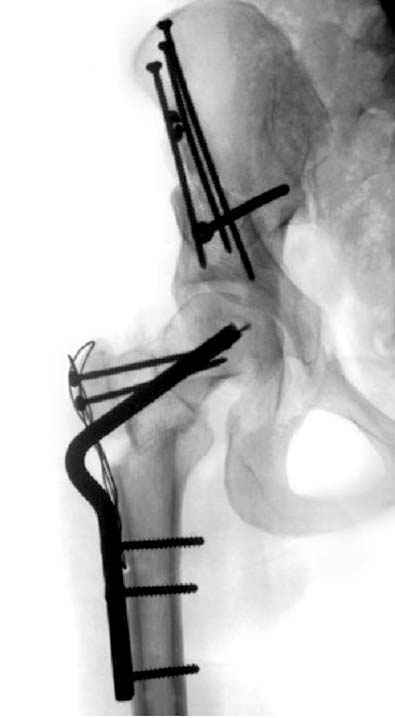

Рис.1 Трехмерная модель тазобедренного сустава с аналогом связки головки бедра. Заметно, что из торца головки выходит капроновый шнур, который с одной стороны прикрепляется к ножке бедренной части модели, а другой его конец, проходя через головку и прикрепляется к вертлужной части модели. Динамометр оказывается не нагруженным, так как аналог связки головки бедра замыкает подвижный узел модели во фронтальной плоскости.

Модель несовершенна, согласен, однако я экспериментировал и с импровизированной илеофеморальной связкой и ацетабулярной губой. Результат был тот же, подвижный узел замыкался посредством аналога СГБ. Для интереса я прилагаю фото., где сымитированы наружные связки и вертлужная губа, но без СГБ видно по показаниям динамометра, что данные структуры незначительно только на 0.5 кг разгружают аналог отводящих мышц. Почему модель получилась именно такой можно рассказать и подробнее если захотите…